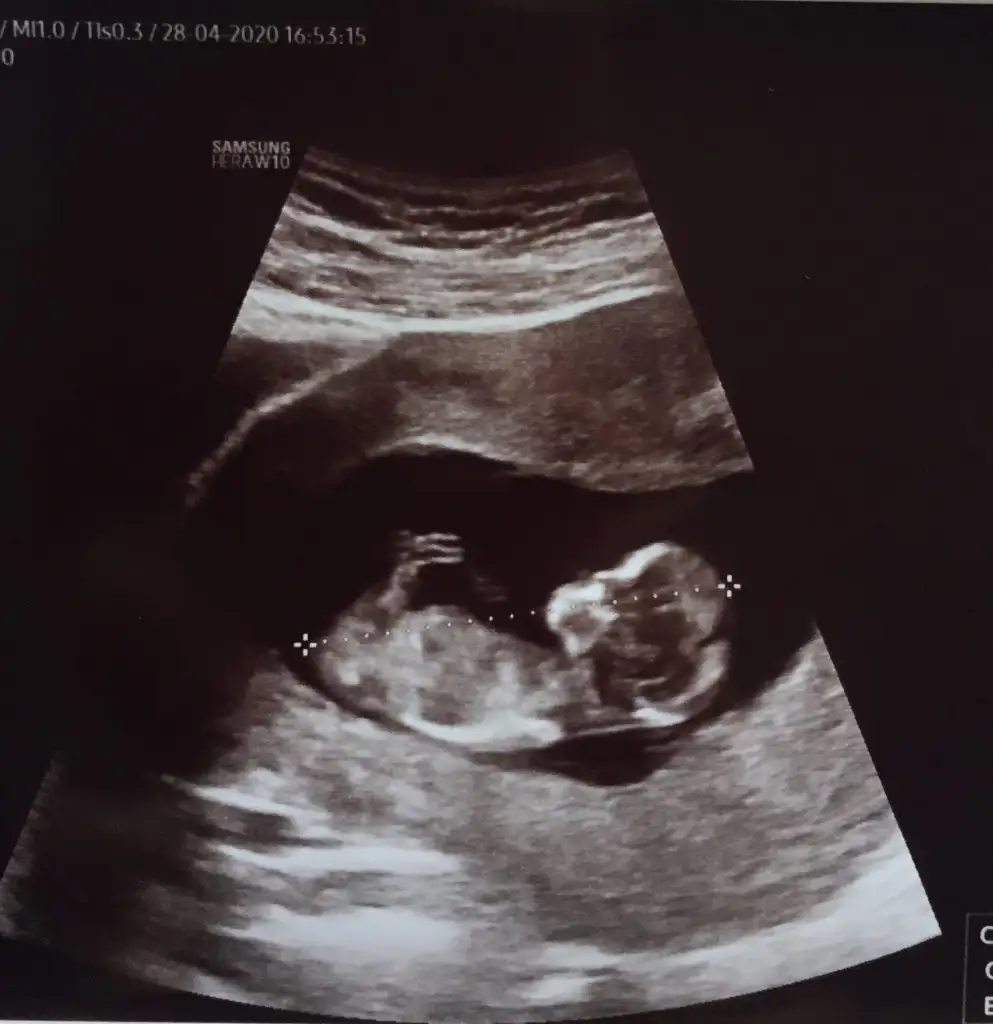

Aynen daha iyi ise usg net tahmin edilirEn net olan buydu ama yarın tekrar kontrolüm var 12+4 olacak olmazsa onu atarım![]()

Net değil sanki erkek gibi siz yinede 12-13 hafta usgde paylaşın11+3 günlük gebeyim rica etsem babada cinsiyet tahmini yapabilir misiniz?

Erkek gibi 12-13 hafta olursa paylaşın11+1 yorumlar mısınız![]()